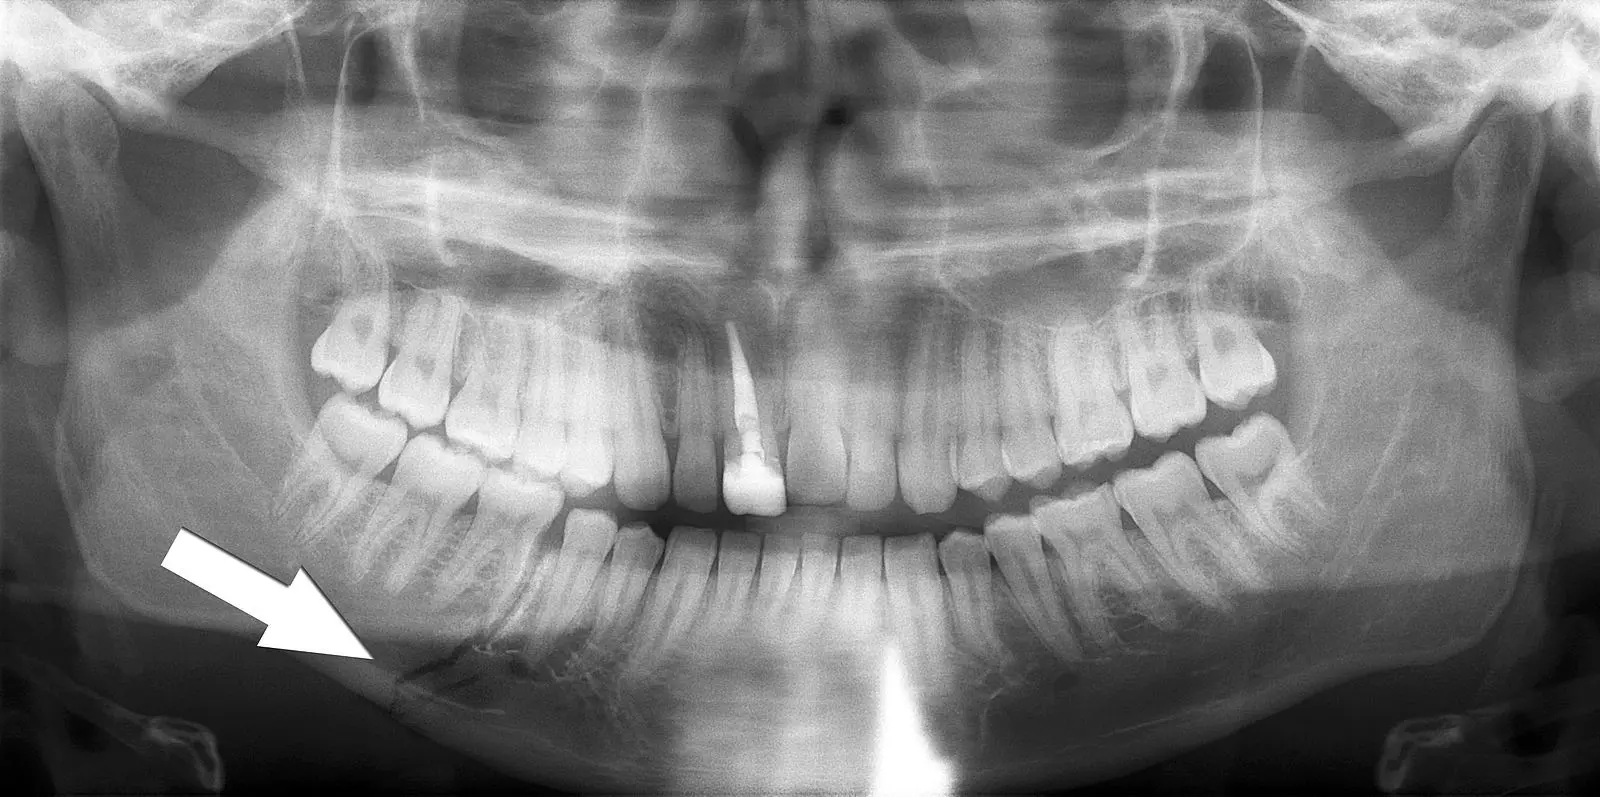

The mandible and temporomandibular joint (TMJ) are assessed with an orthopantomogram (OPG) and mandible views. The mandible commonly fractures in two places, or is accompanied by dislocation of the TMJ.

Image - Orthopantomogram showing a fracture through the body of the mandible

Creative commons source by Coronation Dental Specialty Group [CC BY-SA 4.0 (https://creativecommons.org/licenses/by-sa/4.0)]